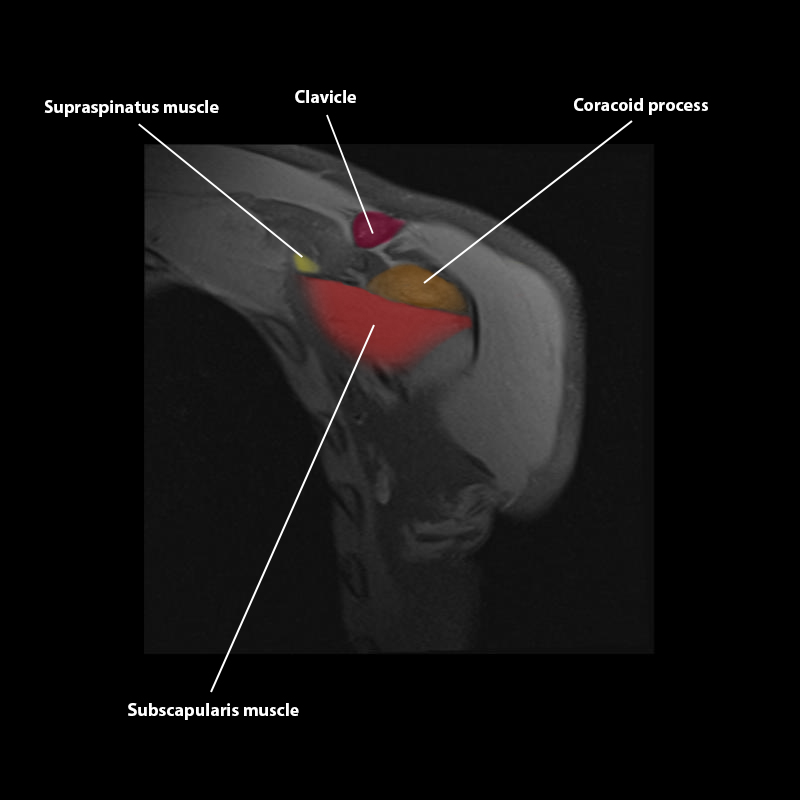

Shoulder MRI Anatomy